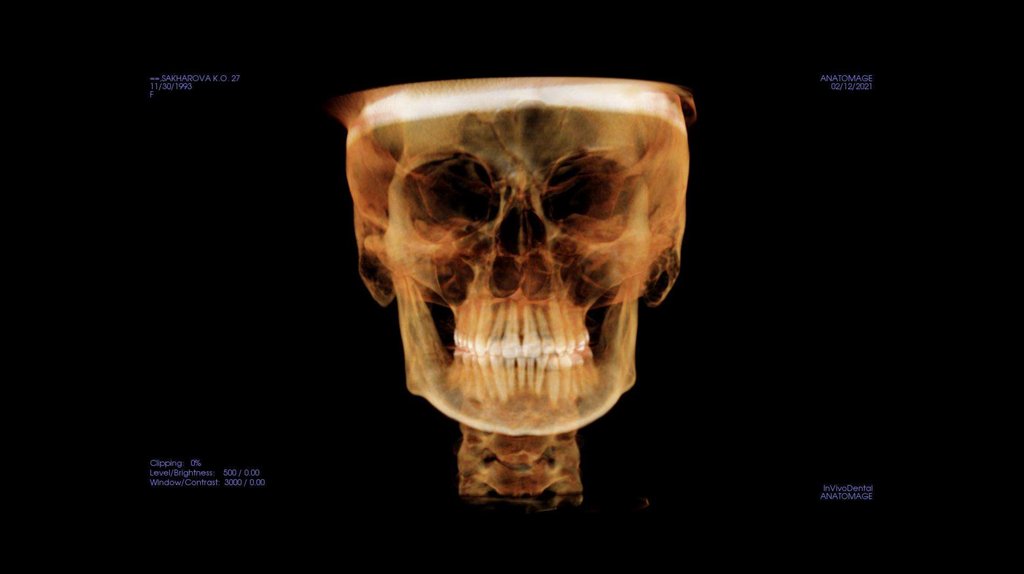

По рассчетам снимков:

• Ретрузия резцов верхней челюсти

• Компрессия головок суставов, особенно правого( началось

ремоделирование)

• Костная ассиметрия(10 мм)

• 2 класс

• 25, 46 зуб – нуждается в санации

• Требуется профессиональняа гигиена полости рта

• Клиновидные дефекты 43, 44

• 18, 28, 38, 48 отсутствуют.